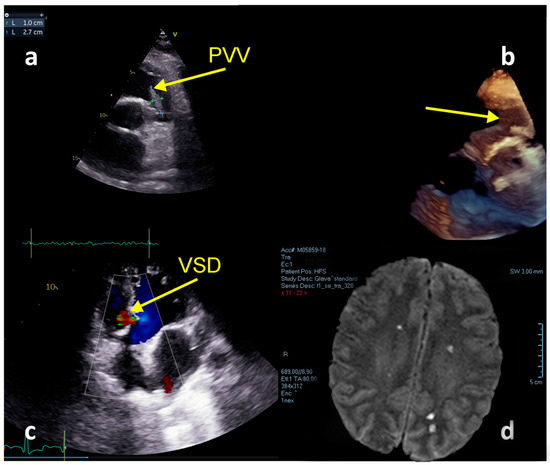

2.3. Case Report No 3